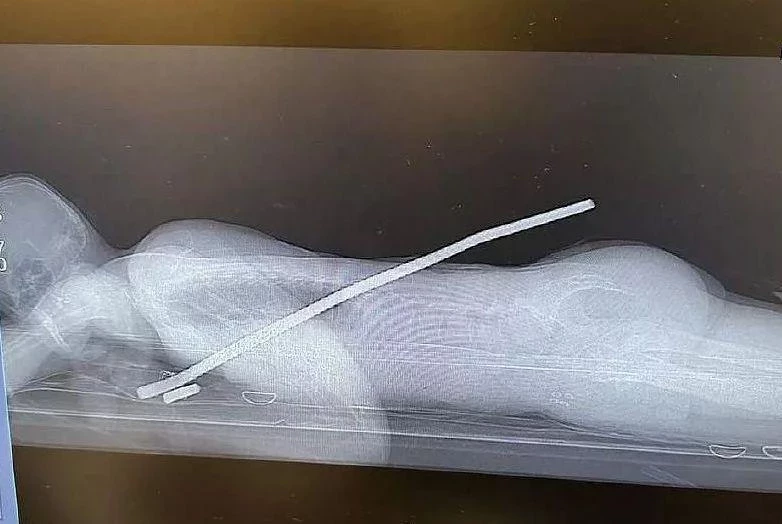

Пациент был доставлен в медицинское учреждение в тяжелом состоянии, и его дыхание было сильно затруднено. Согласно рассказу родственников пострадавшего, он случайно проглотил куриную кость во время обеда, и этот инородный предмет застрял в его гортани.

Благодаря профессионализму отоларингологов и использованию эндоскопа им удалось извлечь куриную кость из горла мужчины. После этой успешной операции дополнительная медицинская помощь пациенту не понадобилась, и он покинул больницу самостоятельно. Пострадавший обещал быть более внимательным и осторожным во время приема пищи, чтобы избежать подобных ситуаций в будущем.